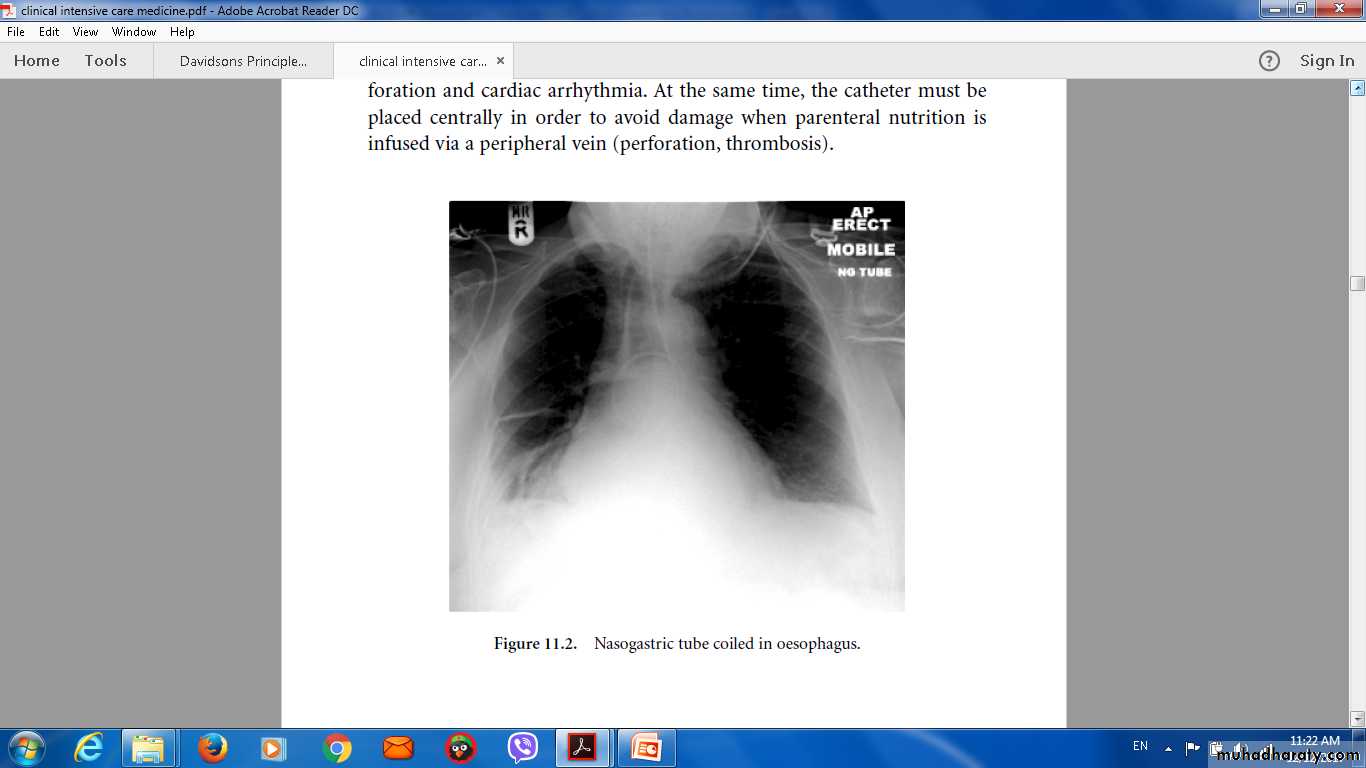

• Nasogastric intubation

New radiological infiltrates.